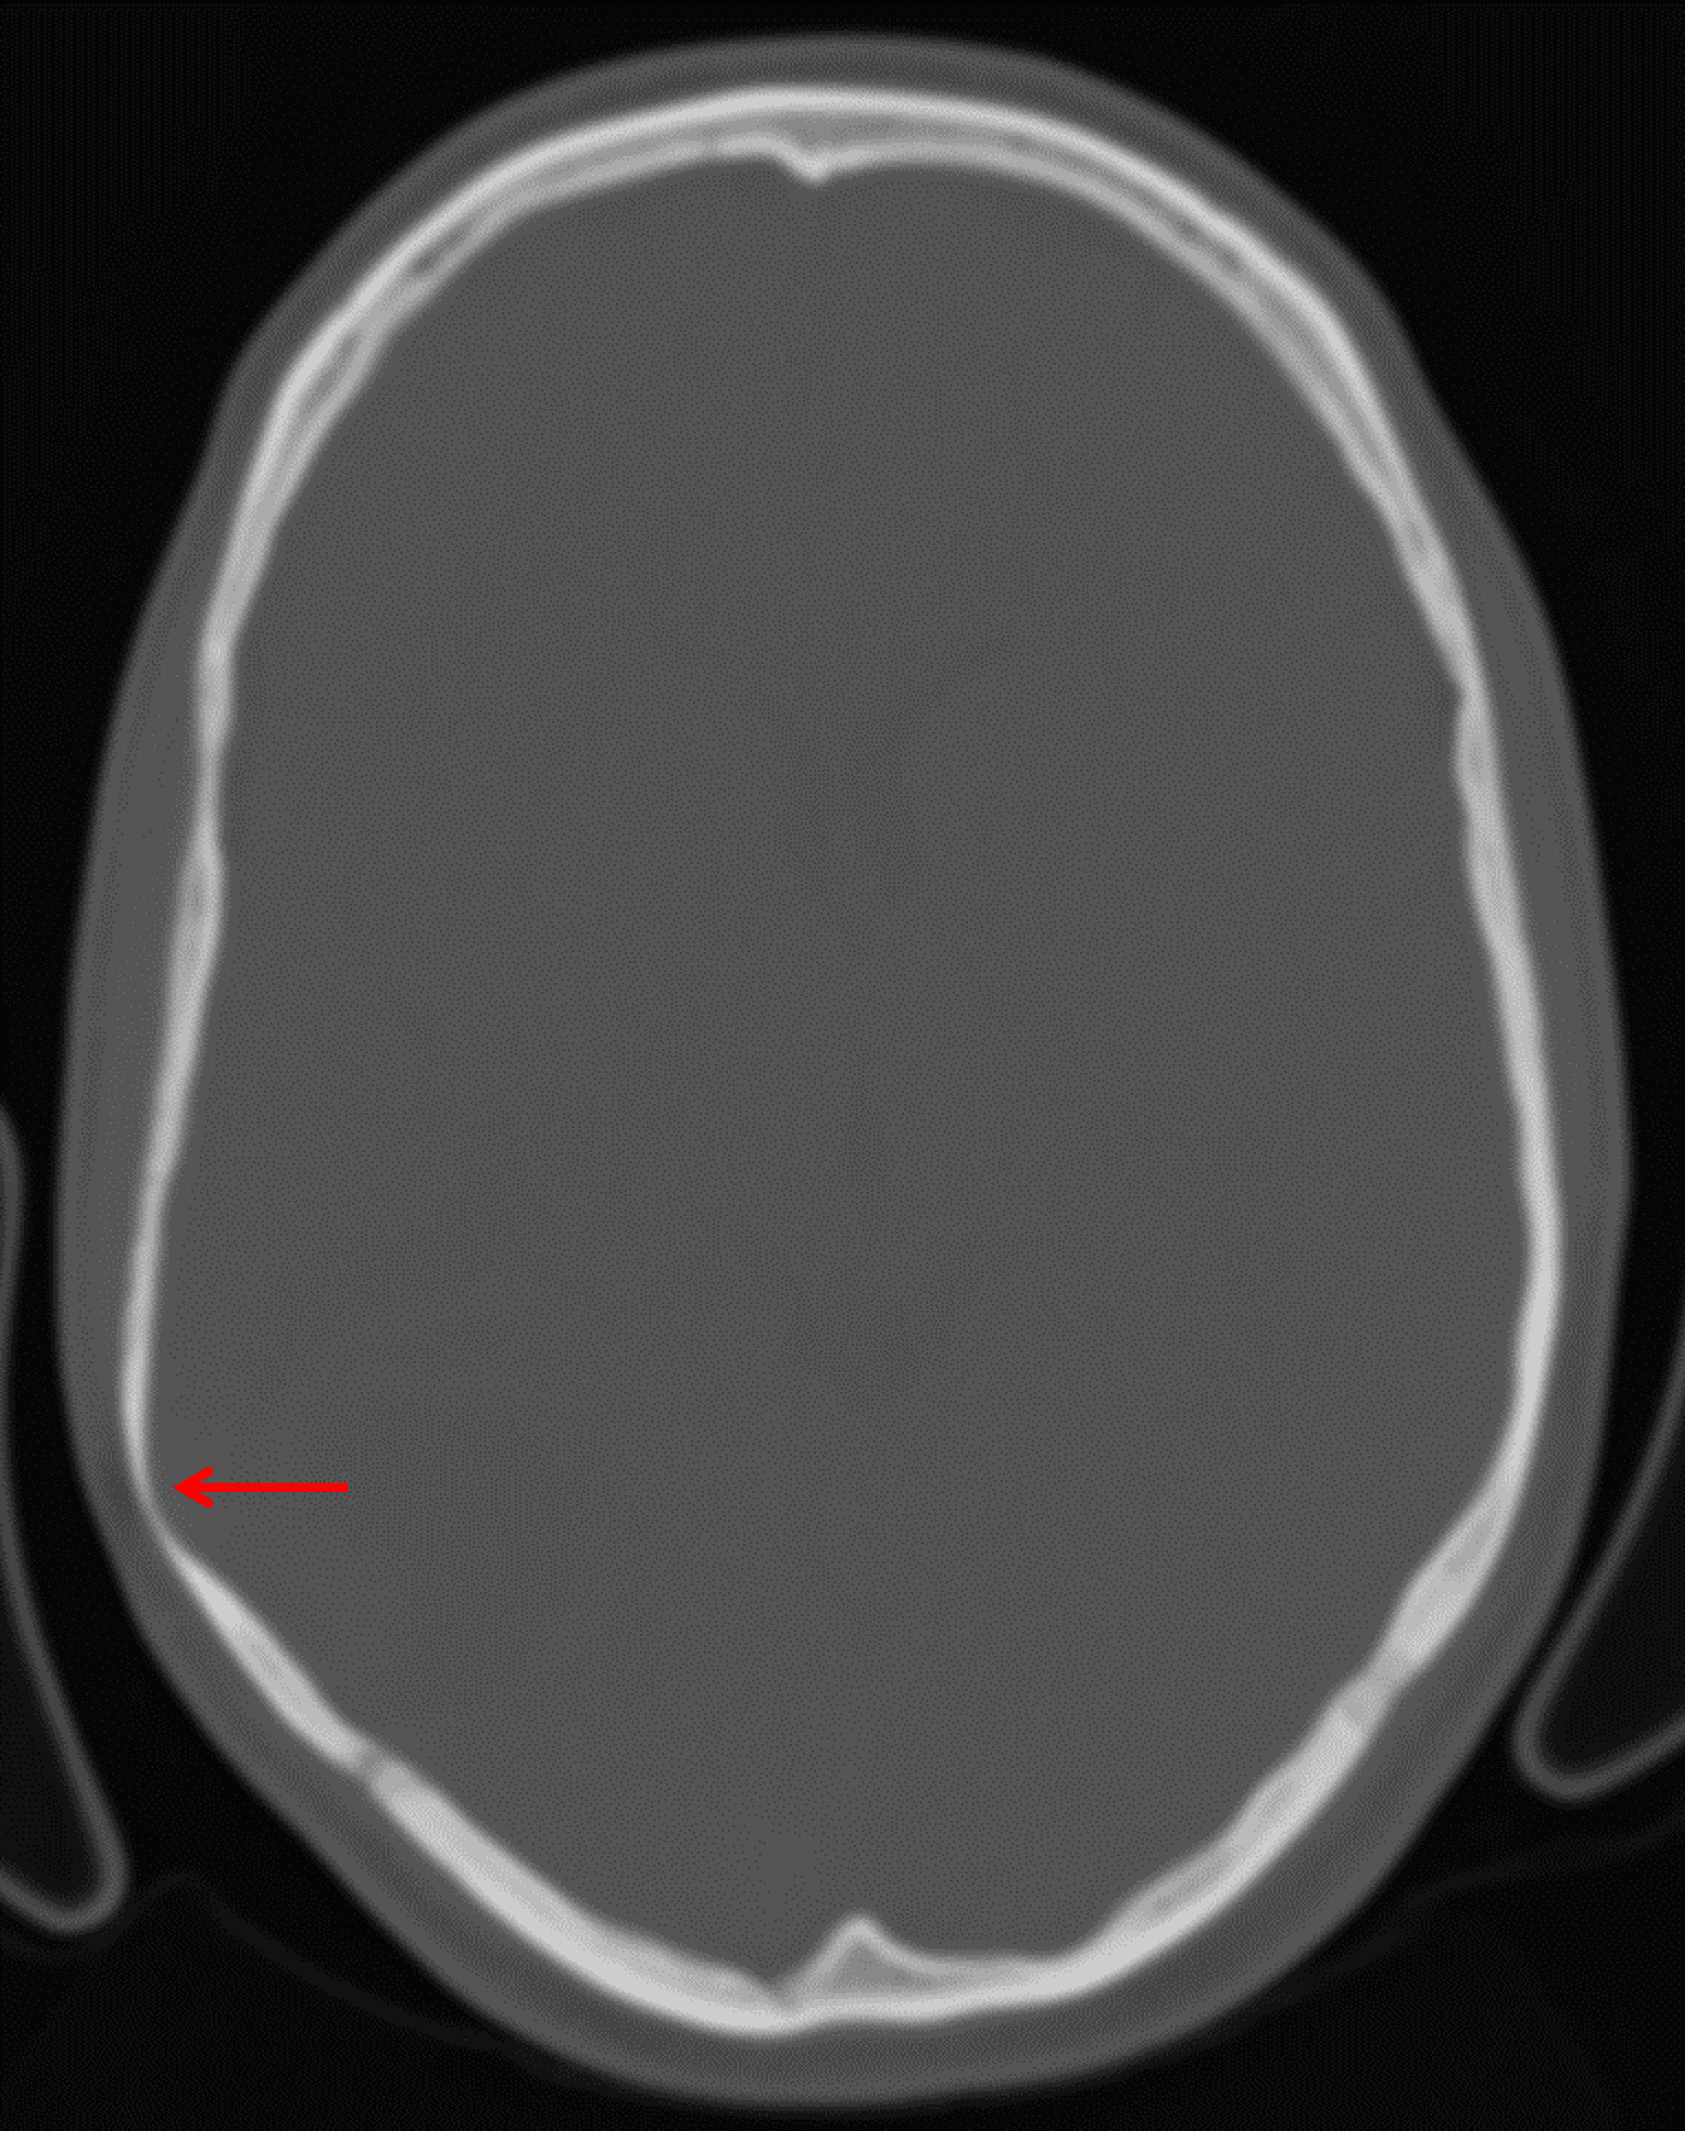

CT

- Mixed attenuation mass with internal calcification centered in the posterior right temporal lobe

- Associated mass effect on the right lateral ventricle without midline shift or hydrocephalus

- Scalloping of the adjacent inner table of the calvarium

Note overlying smooth scalloping of the inner table of the calvarium (red arrow), favoring this to represent a slow-growing tumor.